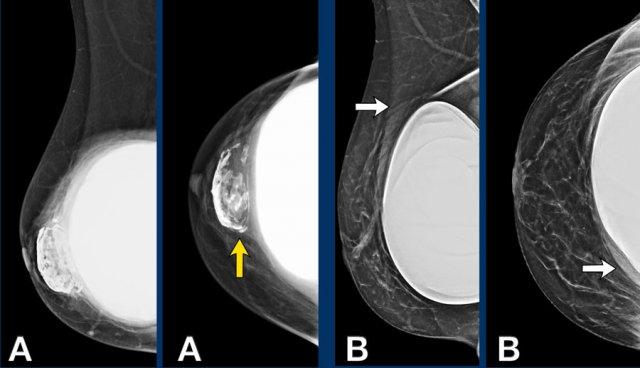

A. Không còn nhìn thấy vỏ bọc xung quanh bề mặt túi độn. Nội dung bên trong hoàn toàn không đồng nhất và thoái hóa.

B. Vỏ bọc bị xẹp (mũi tên vàng) và không đi theo phức hợp vỏ bọc-bao xơ bên ngoài (mũi tên trắng).

Có một khối tập hợp không đồng nhất chứa Silicone nằm giữa vỏ bọc và bao xơ.